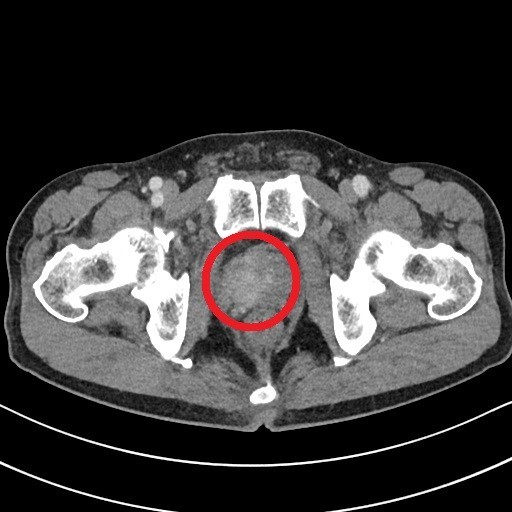

오늘은 남성의 건강을 지키는 중요한 기관, 전립선에 좋은 음식에 대해 이야기하려 합니다. 전립선은 방광 아래에 위치하며 정액을 구성하는 액체를 생산하는 기관입니다.